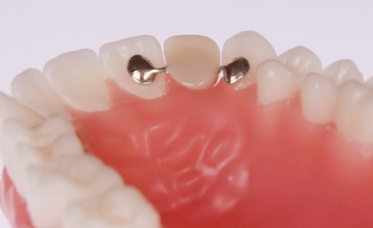

პროტეზირების ეს ტექნიკა პირველად მერილენდის უნივერსიტეტში შემუშავდა და მისი სახელწოდებაც აქედან მოდის. მას “ადჰეზიური ხიდის” სახელწოდებითაც მოიხსენიებენ. თავდაპირველად იგი წარმოადგენდა მეტალის კარკასზე დამაგრებულ ხელოვნურ კბილს. მეტალის “ფრთები” გვერდითი კბილების უკანა ზედაპირზე მაგრდებოდა ისე, რომ კბილის დამუშავება საჭირო არ იყო. რამდენადაც ასეთი მიმაგრება შედარებით სუსტია, მერილენდის ხიდი ფრონტალური კბილების აღსადგენად გამოიყენება (დროებით ან მუდმივად).

მეტალის კარკასის გამოყენებისას მერილენდის ხიდის ესთეტიკური მხარე არასახარბიელო იყო, მითუმეტეს რომ ეს ფაქტორი წინა კბილების ზონაში ყველაზე მნიშვნელოვანია. მეტალი ხელოვნურ კბილს ნაკლებად გამჭვირვალეს ხდიდა, ვიდრე ეს ბუნებრივი კბილებისთვისაა დამახასიათებელი.

სტომატოლოგიაში ახალი, თანამედროვე მასალების გაჩენასთან ერთად მერილენდის ხიდის დამზადების ტექნიკა ბევრად გაუმჯობესდა, ისევე როგორ მისი ვიზუალური მხარე. დღეს მისი დამზადება შესაძლებელია მთლიანად მაღალი ხარისხის კერამიკისგან ან ცირკონიუმის ოქსიდისაგან ლაბორატორიული გზით, ან მინაბოჭკოვანი მასალისგან პირდაპირ პირის ღრუში, იმის მიხედვით მუდმივი კონსტრუქცია მზადდება თუ დროებითი. მერილენდის ხიდი დროებით გამოიყენება, მაგალითად, ფრონტალური კბილის ადენტიის ან კბილის ნაადრევად დაკარგვის შემთხვევაში, სანამ იმპლანტაცია ჩატარება იქნება შესაძლებელია. ასევე, იმპლანტაციის შემდეგ შეხორცების პერიოდში ესთეტიკური მიზნით, სანამ იმპლანტზე მუდმივი კბილის გვირგვინის დამაგრება იქნება შესაძლებელი.